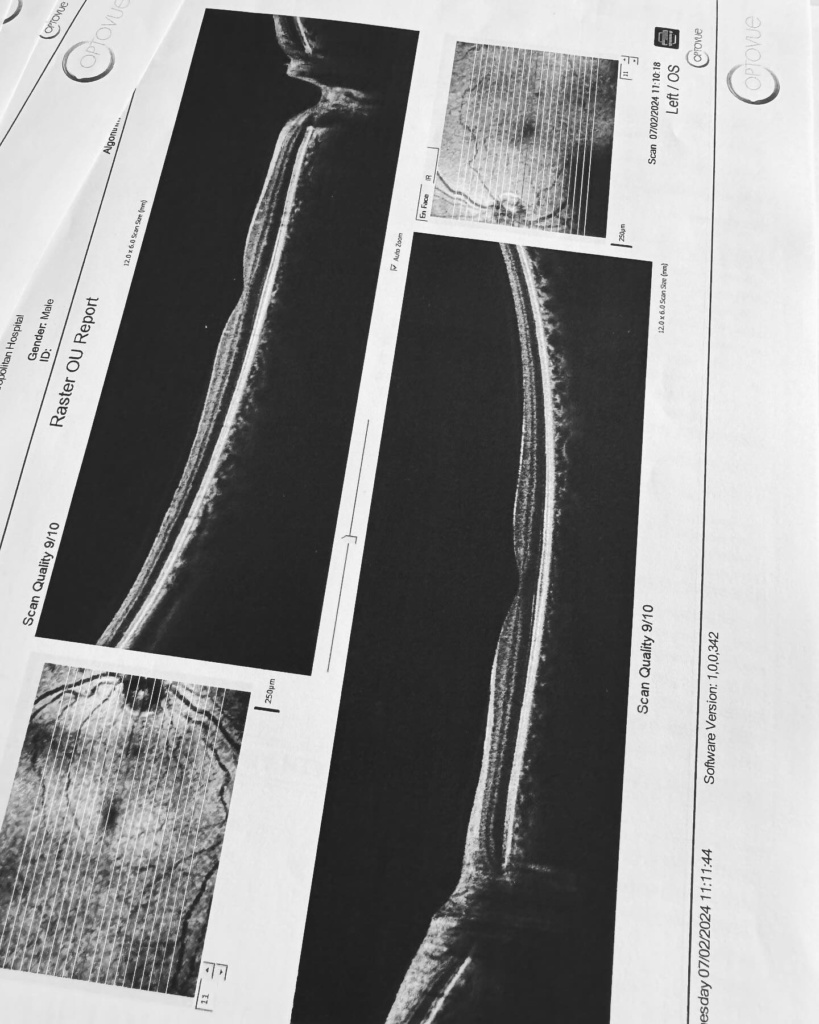

Ή μάλλον για τον τύπο που λέγεται Μάστορας. Ακούω κατά καιρούς διάφορες φήμες και έτυχε να ακούσω και τώρα κάποιες άλλες που δεν τιμούν οποίους τις διαδίδουν οπότε θα ανεβάσω μερικές φωτογραφίες από τις δύο δύσκολες τελευταίες εβδομάδες. Ο πιο σημαντικός λόγος που τις ανεβάζω είναι όμως για να μοιραστώ την ιστορία μου για την αμφοτερόπλευρη δακρυοαδενίτιδα.

Αιτία ο κοβιντ ο άτιμος… Ψάξτε το. Μπορεί και κάποιος από εσάς να υποφέρει από αυτήν αυτό τον καιρό και να μην ξέρει πώς να το διαχειριστεί.. Εγώ μπήκα στο νοσοκομείο και είχα την πιο απίστευτη γιατρό την Δήμητρα Π. να με προσέχει σε κάθε βήμα. Είμαι καλά τώρα όποτε πάμε γερά!», έγραψε χαρακτηριστικά ο Χρήστος Μάστορας.